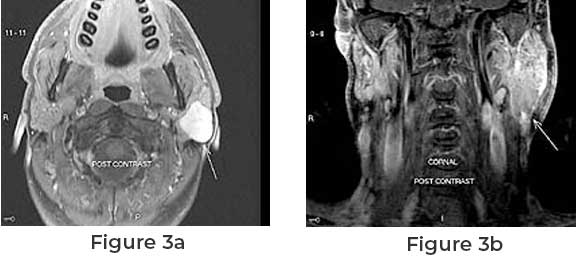

Diagnosis usually involves imaging studies such as CT or MRI scans, followed by a biopsy to determine the tumor’s cellular composition. Treatment typically consists of surgical removal of the tumor, and in some cases, radiation therapy may be recommended, particularly for higher-grade tumors.